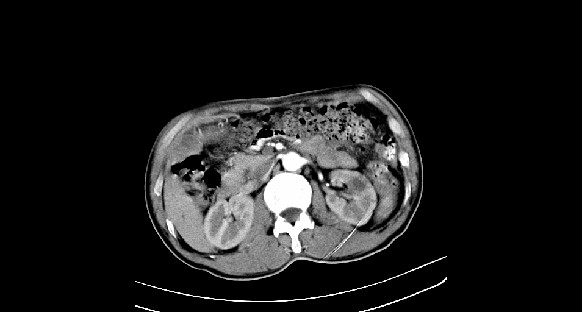

男性,70岁,体检b超发现左肾占位,请各位战友发表一下观点

左肾有两个病灶,且较大的病灶内可见点状钙化灶,增强扫描边缘也是呈渐进性强化,中央部分未见明显强化